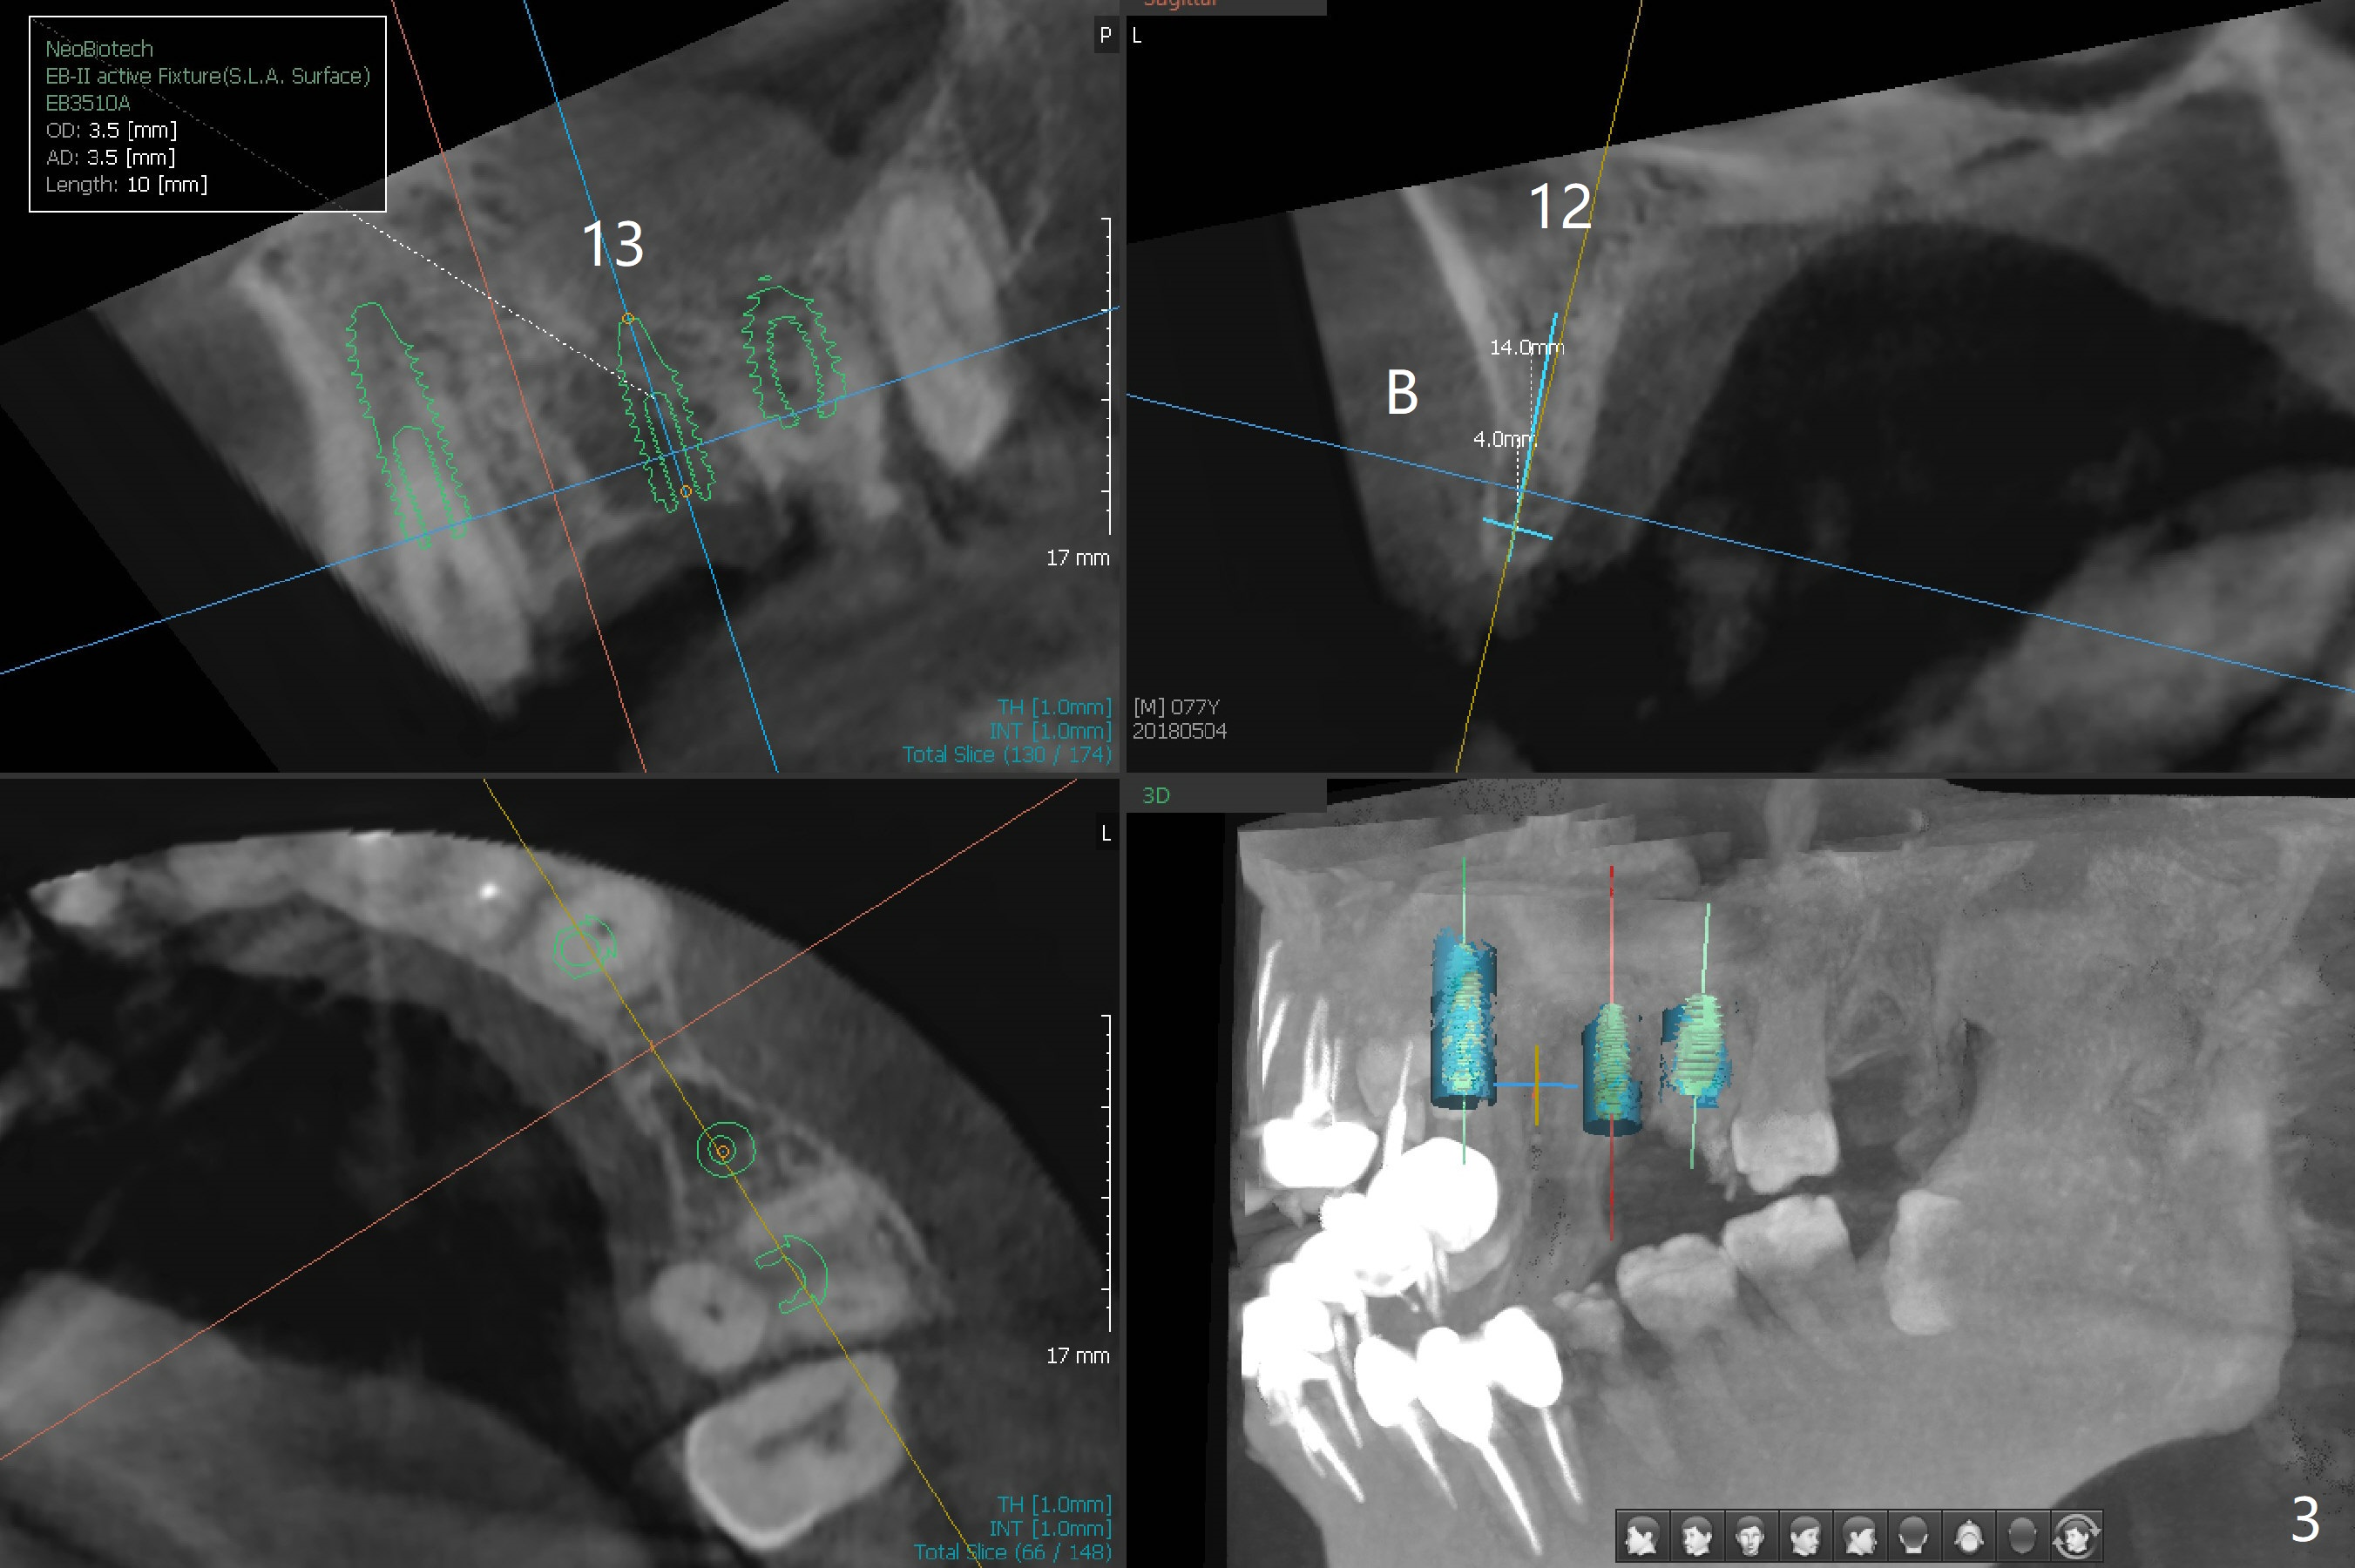

A 77-year-old man has multiple restoration with long roots (suggesting bruxism, Fig.1). The #11-14 FPD dislodges. Twenty days postop, he will travel to his home country and stays for 2 months. Four months postop, he will leave again. To strengthen provisional FPD stability and early final restoration, each implant will be placed at each edentulous area. The longest bone-level implant will be placed at #11 with bone height >20 mm (Fig.2). Since the bone width (buccopalatal) is 4 mm at #12, a 2x14(2) mm 1-piece implant is to be inserted (Fig.3); while a 3.8x10 mm 2-piece one at #13 with underprep because of low density. As the septal bone height is limited at #14 (Fig.4), a 5x8.5 mm implant is going to be placed.